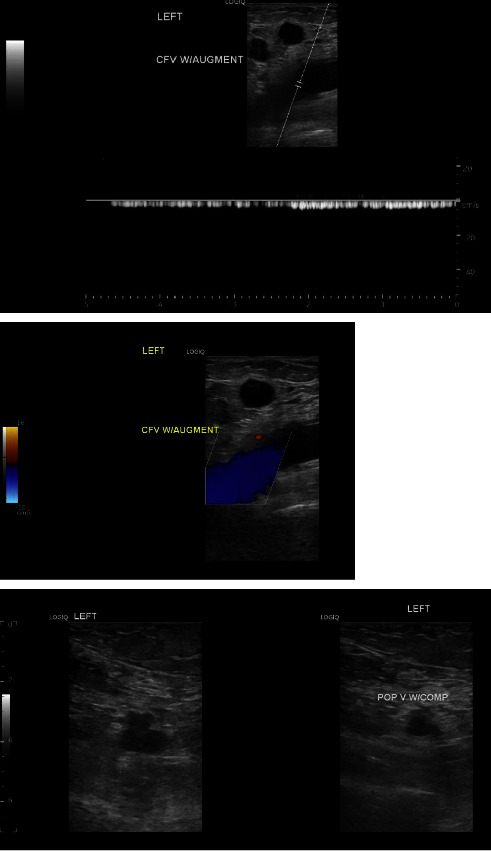

背景:目前,用于探讨癌症患者静脉血栓栓塞症构成的数据极少。本病例报告讨论了一名高级别尿路上皮癌患者的静脉血栓栓塞症状,并重点介绍了血栓的病理学发现。病例介绍。一名 55 岁的女性患者被诊断为高级别尿路上皮癌并有多处转移,左下肢出现广泛的深静脉血栓。由于左下肢疼痛和肿胀,抗凝治疗无效,因此需要进行血管内再通术。医生为她进行了机械性血栓切除术,并将样本送去进行病理检查。病理检查发现了微小的转移癌碎片,并混有层状血块(血栓)。转移癌的形态和免疫染色谱与膀胱转移癌相符:据估计,约有 4-20% 的癌症患者会在某个阶段出现 VTE,确诊后初期的 VTE 发生率最高。每年有 0.5% 的癌症患者会出现血栓,而普通人群的发病率为 0.1%(Elyamany 等人,2014 年)。尽管知道癌症患者的 VTE 发生率增加,但迄今为止分析癌症患者血栓组成的研究却很少。

Background: Currently, minimal data are available to explore the composition of venous thromboembolism in patients with cancer. This case report discusses a presentation of venous thromboembolism in a patient with high-grade urothelial carcinoma and highlights the pathology findings in thrombi. Case Presentation. A 55-year-old female who was diagnosed with high-grade urothelial carcinoma with multiple metastases developed an extensive deep vein thrombosis in her left lower extremity. Endovascular revascularization was indicated due to left lower extremity pain and swelling not responsive to anticoagulation. A mechanical thrombectomy was performed, and samples were sent for pathology. Pathologic examination discovered minute fragments of metastatic carcinoma, admixed with laminated blood clots (thrombus). The morphology of metastatic carcinoma and the immunostain profile were compatible with metastatic carcinoma of bladder origin.